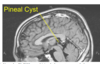

identify

multiple sclerosis

plaque (lesion) in corpus collosum